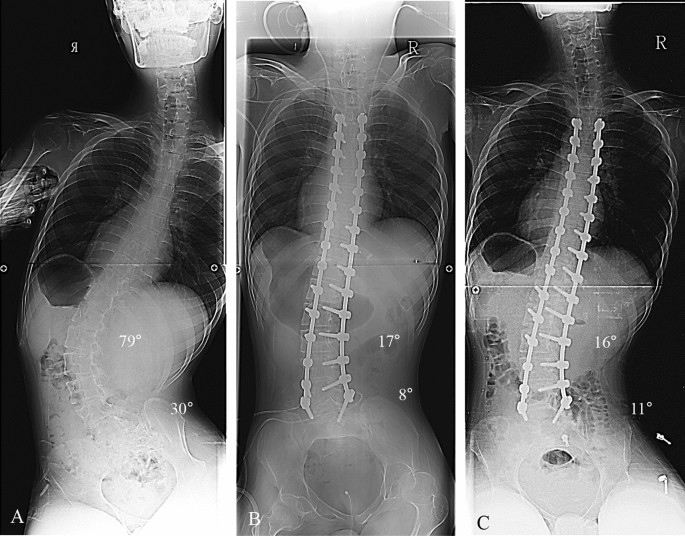

This study was designed as retrospective, comparative analysis at a single institute where deformity correction was routinely performed. All deformity correction procedures were performed by a senior spine surgeon with vast experience in performing standard open surgeries. Considering the effect of pelvic fixation on surgical outcomes, we enrolled patients with NMS who underwent deformity correction from 2009 to 2016. Patients with Cobb’s angle less than 40º and/or PO less than 15º were excluded in our study. A total of 77 patients was included and divided into three groups as follows: the pelvic fixation group (n = 16, NMS patients who underwent pelvic fixation) (Fig. 1), fixed to S1 group (n = 33, NMS patients who underwent fixation to S1 without pelvic fixation) (Fig. 2), and fixed to L5 group (n = 28, NMS patients who underwent fixation to L5 without pelvic fixation) (Fig. 3). This study was performed after obtaining approval of the institutional review board of Korea University of Guro Hospital. The present study was performed in accordance with the contemporary amendments of the Declaration of Helsinki and within an appropriate ethical framework. Both children and parent and/or legal guardians were informed of the purpose of the study, agreed to participating, and signed informed consent for both study participation and publication of identifying information/images in an online open-access publication.

Deformity correction from T4 to L5 in patients with neuromuscular scoliosis (NMS). (A) A 16-year-old male patient who diagnosed with Duchenne muscular dystrophy showed neuromuscular scoliosis. The whole-spine anterior–posterior image showed 79° of scoliosis deformity, and pelvic obliquity was 30° as measured by pelvic tilting angle. (B) The immediate postoperative radiograph showed 17° of the Cobb’s angle (78.4% of correction rate) and 8° of the pelvic tilting angle (73.3% of correction rate, which are not performed by spinopelvic fixation). (C) The last follow-up Cobb angle showed 16° and pelvic obliquity was 11°.